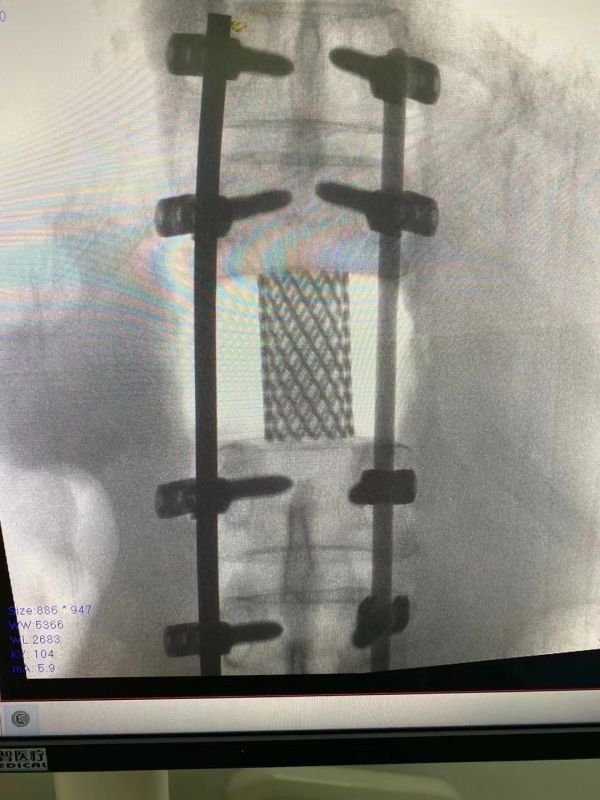

武汉市第五医院骨科刘洋主任团队经过会诊,选择施行后路全椎体切除及重建术,缓解对神经的压迫,重建脊柱功能,最大程度切除肿瘤并保护患者神经功能。

5月23日下午6时,历时7小时椎体肿瘤切除及重建术圆满完成,赵大爷脱离生命危险,疼痛缓解,神经功能得以正常保留,进入后期康复阶段。

骨科主任刘洋介绍,赵大爷肿瘤从胸椎内部长出,已将椎体侵蚀近3/4,导致边缘剩余骨质脆弱。若持续进行行走、坐立活动,极可能发生严重的病理性骨折从而压迫脊髓神经引发下肢瘫痪及大小便功能障碍,导致严重的残疾甚至危及生命。